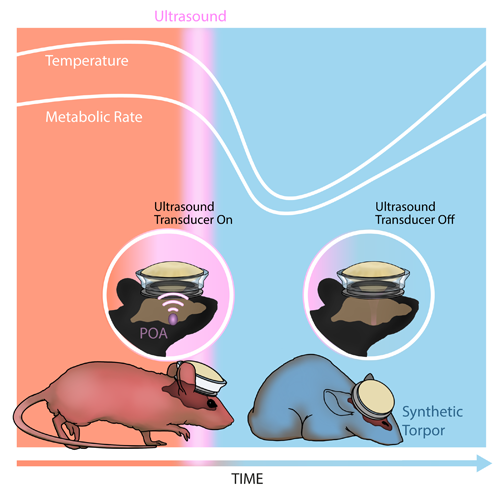

- Closed-Loop Transcranial Ultrasound Stimulation for Real-Time Non-invasive Neuromodulation